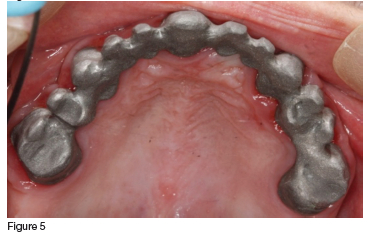

In consultation with the patient, it was decided that, although compromised, the clinician would try to save all the maxillary teeth. Initial treatment included endodontic therapy to address the pulpitis and pain in the fractured 13, followed by crown preparations on all of the remaining maxillary teeth. These were then used as abutments for the definitive prosthesis, which was a telescopic crown-retained porcelain fused to metal fixed partial denture (figures 4, 5 & 6). The mandible was restored with an acrylic veneered implant supported hybrid prosthesis (figure 7).